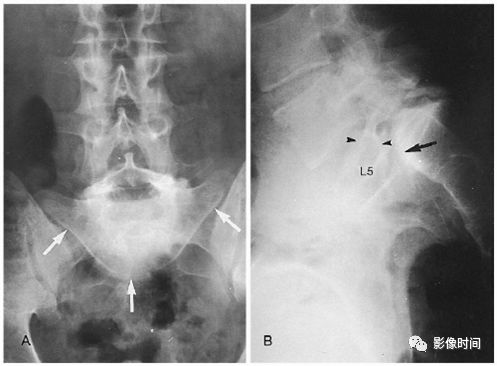

5倒置拿破仑帽征

倒置拿破仑帽征(inverted napoleon hat sign),亦有译为反拿破仑帽征

倒置拿破仑帽征是指在腰椎正位 X 线片中,腰 5 与骶 1 的投影轮廓重叠,形似倒置的拿破仑帽(蓝箭)。其中帽子的边缘是腰 5 的横突形成,而帽子的圆顶是由腰 5 的椎体投影构成。

本征象主要用于描述腰 5 椎体前滑脱(这种滑脱通常为先天性或创伤性,退变性的少见),在腰 5 未滑脱但腰骶部显著前凸时也可以出现此征象。

典型病例

22 岁男性,腰椎侧位片可见腰 5 椎体呈梯形(黑箭头),显著向前、下滑脱(黑箭),正位片形成倒置拿破仑帽征(白箭)。